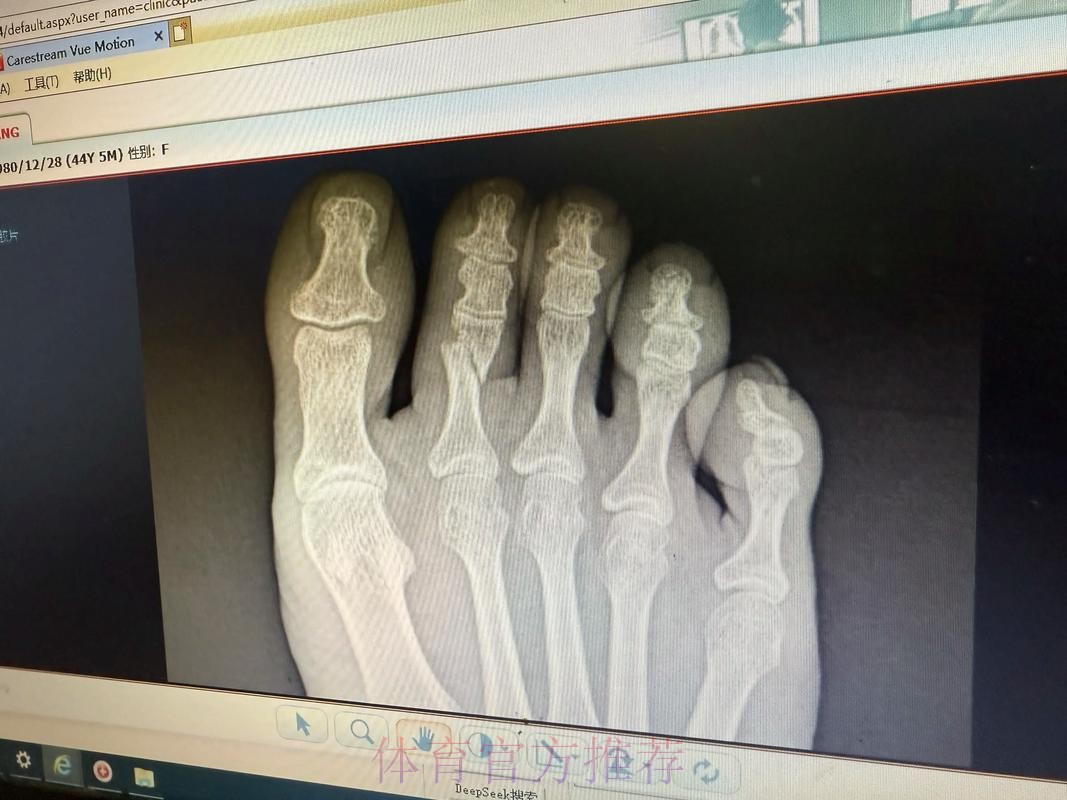

皇马官方伤情通告背后的信号 皇马官方一向在伤病信息上措辞谨慎,但“左脚第二跖骨不完全应力性骨折”这句话本身已经透露出不少关键信息。这是跖骨部位的应力性损伤,而非一次剧烈对抗造成的瞬间骨折,说明问题来自长期负荷积累,是典型的疲劳型伤病。“不完全”意味着骨结构尚未完全断裂,仍保持一定连续性,这对康复时间和方式具有决定性影响。如果处理得当,往往可以通过相对保守的治疗方案避免手术;但一旦急于复出或训练负荷控制不当,就有可能从“不完全”演变为完全性骨折,令缺阵期成倍延长。对于依赖琼阿梅尼在中场完成覆盖和防守平衡的皇家马德里来说,如何在争冠压力下保护好球员、又不让球队竞技水准大幅下滑,将是一场同样艰难的“心理博弈”。

跖骨应力性骨折究竟意味着什么 许多球迷听到“应力性骨折”会下意识以为只是轻微小伤,但在运动医学语境中,这却是对高负荷训练的一种严肃警告。跖骨是足部承重和发力的重要骨骼,足球运动中的短距离爆发、急停变向、频繁起跳落地,都会不断将力量传导至跖骨区域。当训练和比赛的总量超过身体适应阈值,同时恢复时间又不足时,骨组织内部会出现微小裂纹,这些微裂如果得不到及时修复,就逐渐累积形成应力性骨折。不完全应力性骨折通常意味着裂纹尚未贯通骨骼,两侧仍存在结构支撑,因此患者在早期往往还能咬牙坚持训练甚至上场。但正是这种“还能坚持”的错觉,使得应力性骨折在职业足球中极具隐蔽性——当你真正感觉到强烈疼痛时,很可能已经接近完全骨折的边缘。琼阿梅尼的伤情被及时查出,某种程度上说明皇马医疗团队对他的反馈足够重视,也体现了俱乐部在数据监控和身体管理上的专业度。

运动医学视角下的康复和复出节奏 从医学角度看,左脚第二跖骨不完全应力性骨折的康复核心在于“控制负荷”和“逐步恢复”。初期需要通过休息和减压让骨组织完成自我修复,有时会配合使用护靴或拐杖减少足部承重;中期则通过理疗、轻量力量训练和本体感觉训练逐步恢复功能;后期则要加入跑动、变向和带球训练,模拟比赛中的真实对抗场景。真正的难点不在诊断,而在“何时可以回到90分钟高强度比赛”这道关卡。如果皇马在赛程压力或舆论压力下过早安排琼阿梅尼复出,哪怕他在短时间内状态看似良好,也可能埋下复发或二次伤病的隐患。对球员而言,学会倾听身体信号,与医疗团队保持坦诚沟通,避免“硬扛文化”的主导,也是职业生涯能否拉长的重要因素。